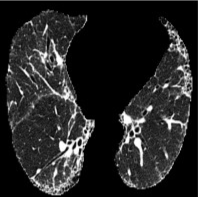

Based on Eqn. (2), we can identify the most influential cluster contributing to the final score for each individual by vectorizing the feature for each cluster. The heatmap in Supplementary Fig. 2 represents the contribution of the cluster to the final patient-level risk score on the FLD dataset, where the panels from left to right depict the vectors for patients arranged in decreasing order of value. The rationale behind each patient’s final prediction: the red cube highlights clusters contributing to high-risk scores, while blue indicates a lower risk. From this visualization, we can see that patients with different prediction results are highly disentangled, and the contributing patterns are clearly delineated for each patient. The most influential clusters across the dataset are determined by comparing the average values between the two classes with different predictions. The ranking of clusters by contribution to the ‘mortality in one year’ class on the FLD dataset is shown in Supplementary Fig. 3 and the most representative slice patterns are provided in Supplementary Fig. 4, which show that the model can identify common clusters within each class group, enabling us to pinpoint most significant features by visualizing the most frequently contributing clusters among patients.